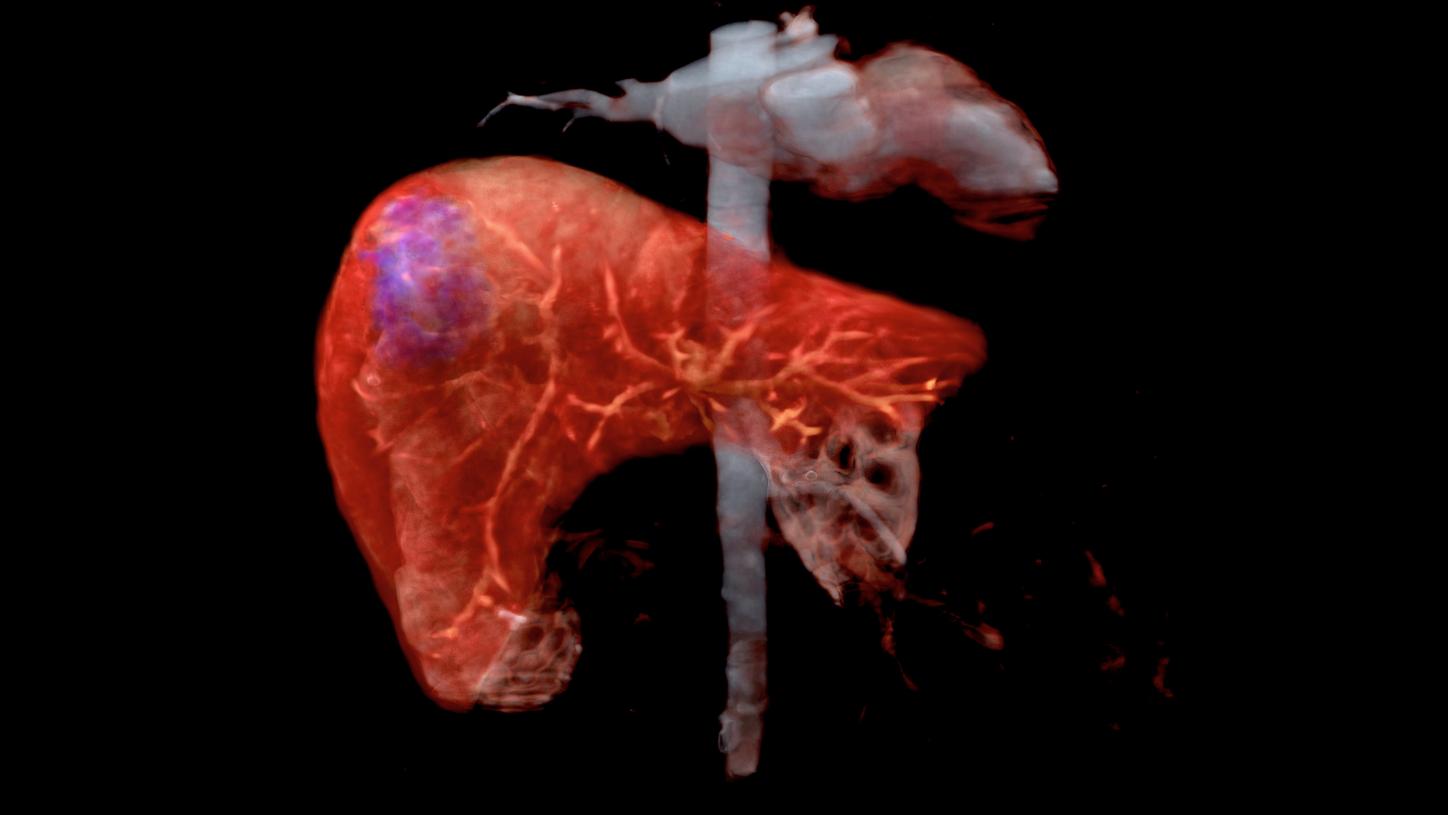

Liver cancer: Imaging of the liver used for cancer diagnosis

Liver cancer

Every year, almost one million people around the world are diagnosed with hepatocellular carcinoma - the most common type of liver cancer. As a complex, multi-faceted disease, liver cancer can be difficult to treat, as treatment methods will depend on liver function levels and performance, as well as the progression stage of the tumor. Image-guided procedures can support the treatment of liver cancer by providing medical practitioners with digital image data for diagnosis, risk stratification, and treatment planning in the early stages of detection, as well as guidance and support during care.